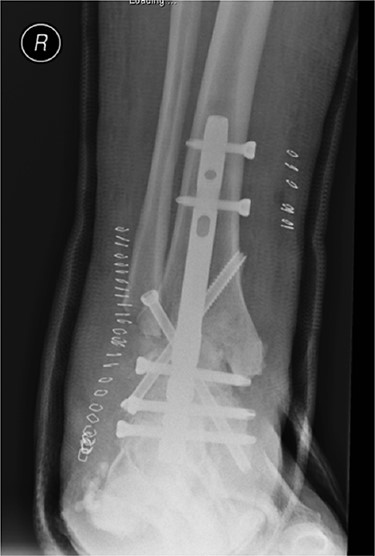

Anterior–posterior radiograph of right ankle demonstrating tibiotalocalcaneal fusion using a hindfoot nail and screws.

Preoperatively, radiographs were used to template and to determine the size of the nail. The canal was over reamed by 4 mm: 2 mm of which accommodated for the Cerament mantle, with a further 2 mm to minimise friction during nail insertion. Reamings were sent to microbiology. The canal was washed thoroughly with saline pulsed lavage, gloves were changed and the patient re-draped.

A BIOMET hindfoot nail was attached to its jig and prepared using a single preparation of 10-ml Cerament-V. When in its fluid phase, the Cerament-V was passed through a syringe to cover the nail. The nail was rotated during the setting process such to attain a uniform and smooth surface (Figs 6 and 7). A 14 mm gauge was used to ensure a 2 mm (× 2) thickness of Cerament was achieved. The nail was subsequently inspected such to exclude any defects in the mantle. There was adequate time to ensure that the Cerament had set. Interlocking screw holes were not sited as this may have damaged the cement mould.

The nail was inserted under guidance from fluoroscopy. Proximal and distal locking was performed through the standard jigs (Fig. 8).